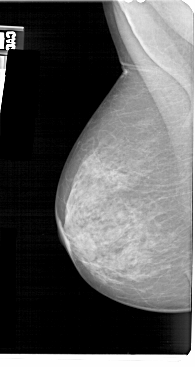

A_1465_1.RIGHT_MLO

RIGHT_MLO LINES 5491 PIXELS_PER_LINE 2776 BITS_PER_PIXEL 12 RESOLUTION 43.5 OVERLAY